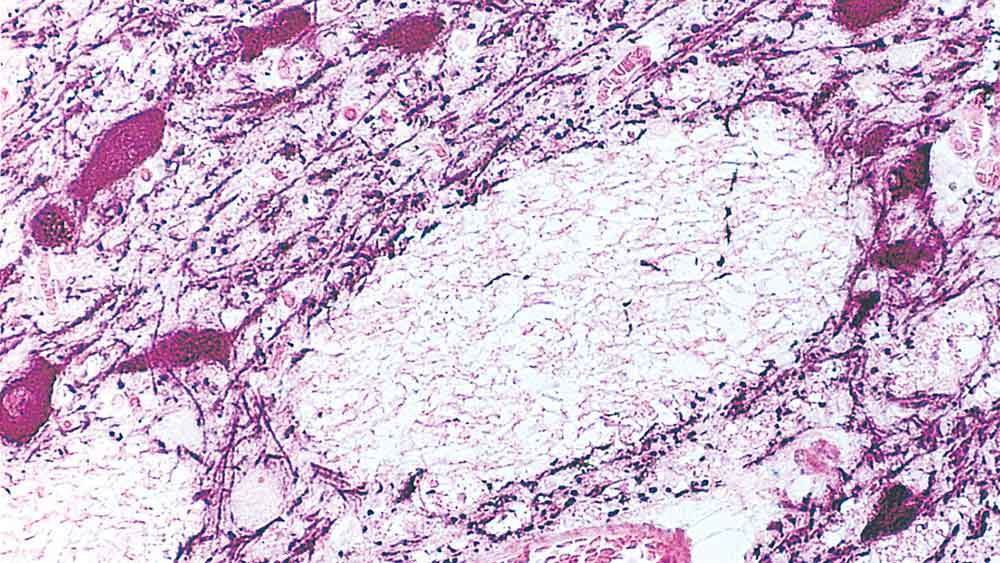

Human midbrain: immunohistochemical staining of Tyrosine Hydroxylase enzyme. Note cytoplasmic staining of catecholaminergic cells and their processes. (Peroxidase substrate: nickel DAB, Counterstain: eosin). Tyrosine Hydroxylase: clone 1B5

Antigen Background

TH is reactive with tyrosine hydroxylase in human, mouse and rat brain tissue.